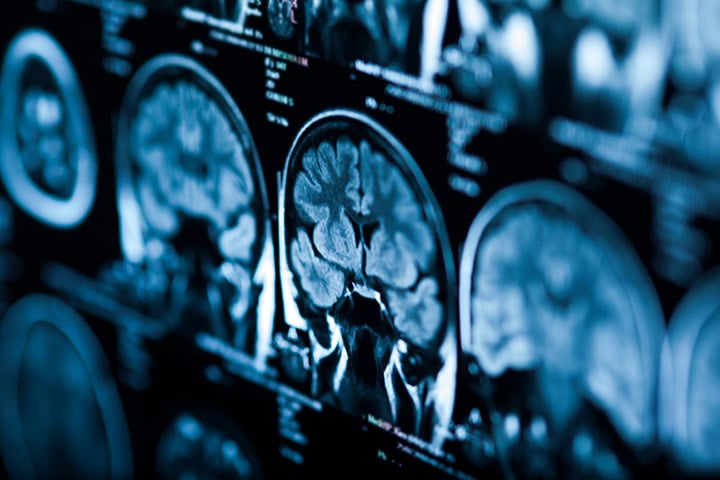

Il s’agira de développer un nouveau paradigme intégrant santé des populations et innovation thérapeutique pour lutter contre les maladies neurologiques les plus courantes, les accidents vasculaires cérébraux et la démence, et promouvoir un bien vieillir cérébral. Ce nouvel Institut sera au cœur d’une dynamique globale émergente axée sur l’innovation et l’inclusion, visant à maximiser l’impact scientifique, médical et socio-économique des recherches en santé vasculaire cérébrale, aux niveaux national et international.